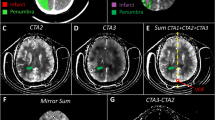

Table 3 summarizes the agreement and accuracy of classifying CTP diagnostic criteria with dCTP and mCTA-P. Forty-six patients had a favourable mismatch profile as determined by standard CTP. A substantial agreement (κ = 0.75, 95% confidence interval [CI]: 0.56–0.94) was found between CTP and dCTP mismatch profiles whereas agreement was moderate with mCTA-P (κ = 0.48, 95% CI: 0.22–0.74). Using CTP mismatch profiles as the ground truth, classification accuracy was 90% with dCTP and 82% with mCTA-P. Overall, mCTA-P had weaker specificity for identifying an unfavourable mismatch than sensitivity for a favourable profile. Figures 3 and 4 show examples of a concordant and discordant mismatch profile using mCTA-P versus CTP.

Patient presenting 5 h after stroke symptom onset with an occlusion of the right internal carotid to M1 middle cerebral artery and an NIHSS of 22. This patient did not receive reperfusion treatment. (A.i) Admission non-contrast CT shows early ischemic changes in the right MCA territory; (A.ii) maximum intensity projections of CT angiography with the red arrow indicating the occlusion site; (A.iii) follow-up non-contrast CT showing infarction and hemorrhage outlined in red. (B.i) CT perfusion ischemic core (red, 84.0 ml) and penumbra (green, 236.8 ml; mismatch ratio of 2.8) derived from cerebral blood flow (B.ii) and Tmax maps (B.iii). DEFUSE-3 mismatch was unfavourable by CT perfusion due to the large core volume. (C) Similarly, down-sampled CT perfusion (dCTP) indicated an unfavourable mismatch profile with an ischemic core and penumbral volumes of 71.7 ml and 205.3 ml, respectively (mismatch ratio 2.9). (D) Multiphase CT angiography-perfusion (mCTA-P) showed a similar ischemic lesion, but underestimated ischemic core and penumbra at 58.0 ml and 202.5 ml, respectively (mismatch ratio 3.5), leading to a favourable DEFUSE-3 mismatch profile and disagreement with CTP.